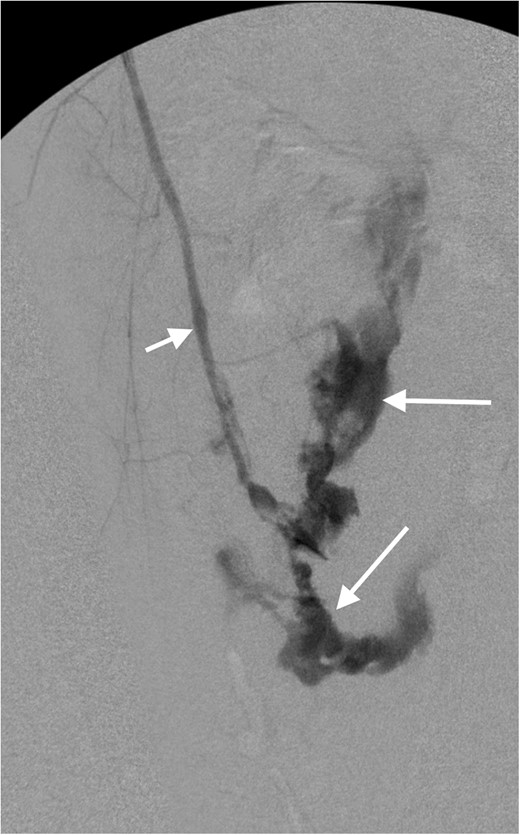

The patient underwent fasciotomy of the left thigh with no return of his pulses. Following this, an intraoperative arteriogram was performed (Fig. 2), demonstrating extensive extraluminal extravasation of contrast from the popliteal artery and no opacification of arteries distal to the knee; these findings are consistent with popliteal artery transection. The patient had a left lower leg fasciotomy and vascular bypass, from the superficial femoral artery to the distal popliteal artery, using a contralateral saphenous vein graft, with successful restoration of distal pulses.

Intraoperative arteriogram of the left lower extremity demonstrates opacification of the superficial femoral artery (short arrow). There is extensive extraluminal extravasation of contrast (long arrows) from the popliteal artery, and non-visualization of the distal vessels, consistent with complete transection of the popliteal artery.